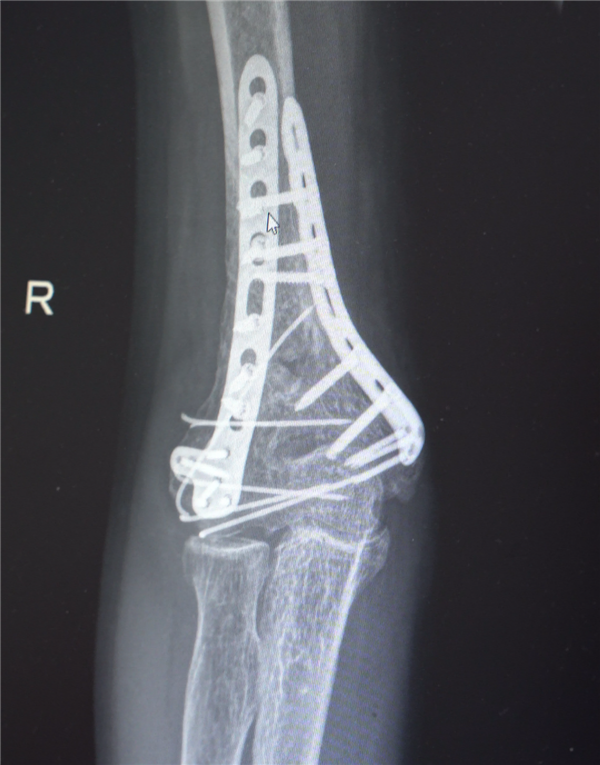

鉴于男子多处骨折,其中最严重的当属右肘部C3型粉碎性骨折,关节面及髁上严重粉碎(碎成了七块),肘关节易粘连,复位固定难度极高。

最终医疗团队采用了“拼古董”式复位固定技术,就像修复一件珍贵的古董瓷器,先拼接大块骨块再贴合小块,先后进行了两次手术。